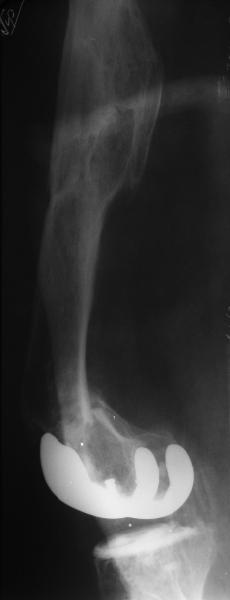

Добрый день! В нашу больничку поступил пациент после бытовой травмы - упал, подвернув ногу. На RG-граммах перелом дистального метаэпифиза бедренной кости. Пациент спутанно рассказывает, где и как он лечился раньше.10 лет назад - коррегирующая остеотомия по поводу деформирующего артроза коленного сустава, 3 года назад в 1 градской больнице г. Москвы выполнено эндопротезирование коленного сустава,площадка большеберцовой кости, со слов пациента, деформировалась около года назад (на фоне остеопороза). Сейчас получил травму в результате падения с высоты собственного роста.Что посоветуете?

Видимо, самое "модное" на сегодня - малоинвазивный остеосинтез пластиной с угловой стабильностью. Распространенный вариант и закрытый интромедуллярный остеосинтез ретроградно. Хотя у нас было бы сделано антеградно - лешево и сердито, действительно малоинвазивно, в сустав не надо влезать. Нет риска прорезания порозной кости с миграцией в сустав, что возможно при ретроградном - гвоздь вводится через вырез в бедреннм компоненте, туда же может и вывалиться. А антеградный - упрется в протез. Как раз вчера заходил больной через полтора года после такой операции. Снимки в приложении.

Перелом имеет хорошие шансы срастить и без операции, однако ось хорошая вряд ли при этом останется. Соответственно, можно будет ждать повторного перелома или нестабильности.